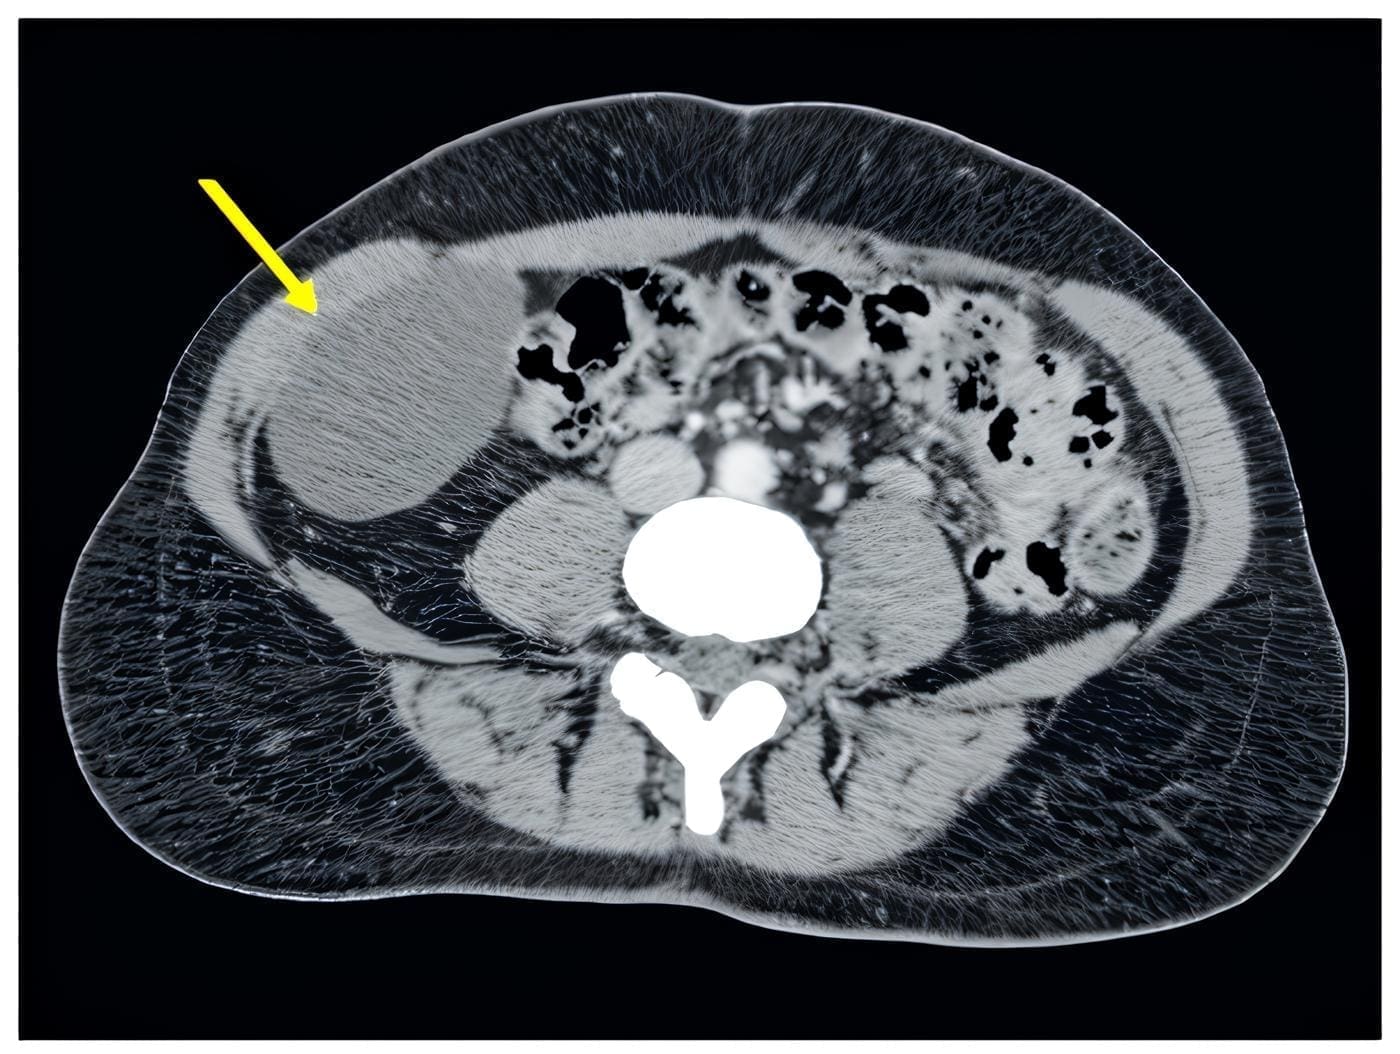

En la tomografía computarizada (figura 1) y en la resonancia magnética (figura 2) de abdomen se observó una lesión de densidad quística, de localización aparentemente extracompartimental en íntima relación con músculo transverso del abdomen derecho, que desplazaba el colon ascendente.

Figura 1. Tomografía computarizada de abdomen donde se aprecia una lesión quística (flecha amarilla), de localización aparentemente extracompartimental, con medidas de 55 x 65 x 85 mm, en íntima relación con el músculo transverso del abdomen derecho, que desplaza el colon ascendente. Fuente: los autores.